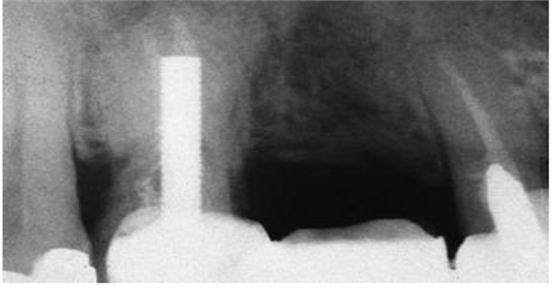

圖2:上頜第一前磨牙的根尖片,過(guò)長(zhǎng)的平行壁樁修復(fù),根尖部的牙膠量少于理想的5mm的根尖封閉

牙髓治療后的牙齒經(jīng)過(guò)樁道的預(yù)備,根尖部的牙膠是抵抗根尖周區(qū)域細(xì)菌傳播的屏障。許多研究結(jié)果都已經(jīng)證實(shí)當(dāng)根尖部的牙膠長(zhǎng)度僅僅是2mm到3mm時(shí),根管內(nèi)存在嚴(yán)重的滲漏;根尖部牙膠量為4mm到5mm能保證充足的根尖封閉。盡管多數(shù)研究結(jié)果都表明4mm的根尖牙膠量能提供充足的根尖封閉,但是樁道預(yù)備時(shí)要精確地達(dá)到4mm是非常困難的,根尖片拍攝角度的差異可能會(huì)導(dǎo)致根尖部保留的牙膠少于4mm。因此在根尖片上,根尖部牙膠5mm比4mm更為對(duì)根尖封閉安全有效。